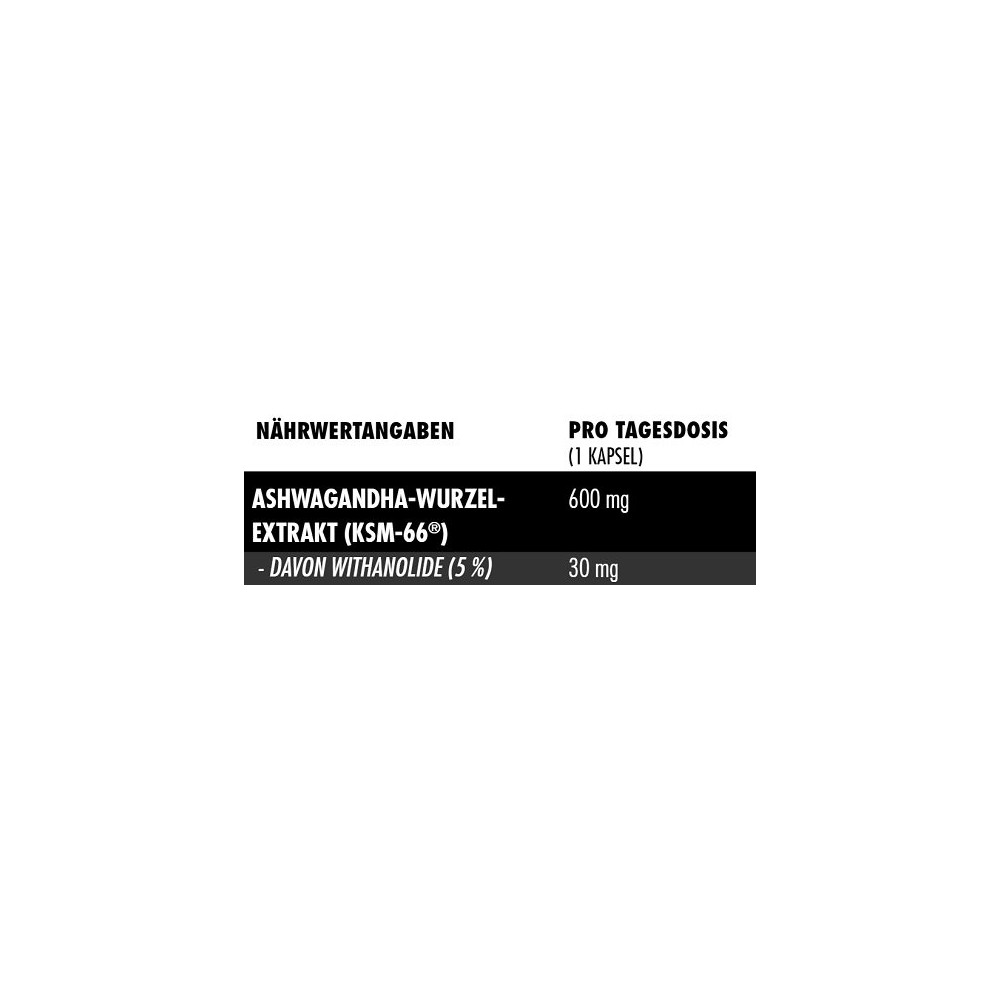

Eine Kapsel Big Zone KSM-66® entspricht 600 mg des patentierten Rohstoffs, welcher auf 5 % Withanolide standardisiert ist. Nehmen Sie je nach Bedarf 1-2 Kapseln täglich mit ausreichend Flüssigkeit ein.

- patentiertes KSM-66®

- Vollspektrum

- xtrakt mit 5 % Withanoliden